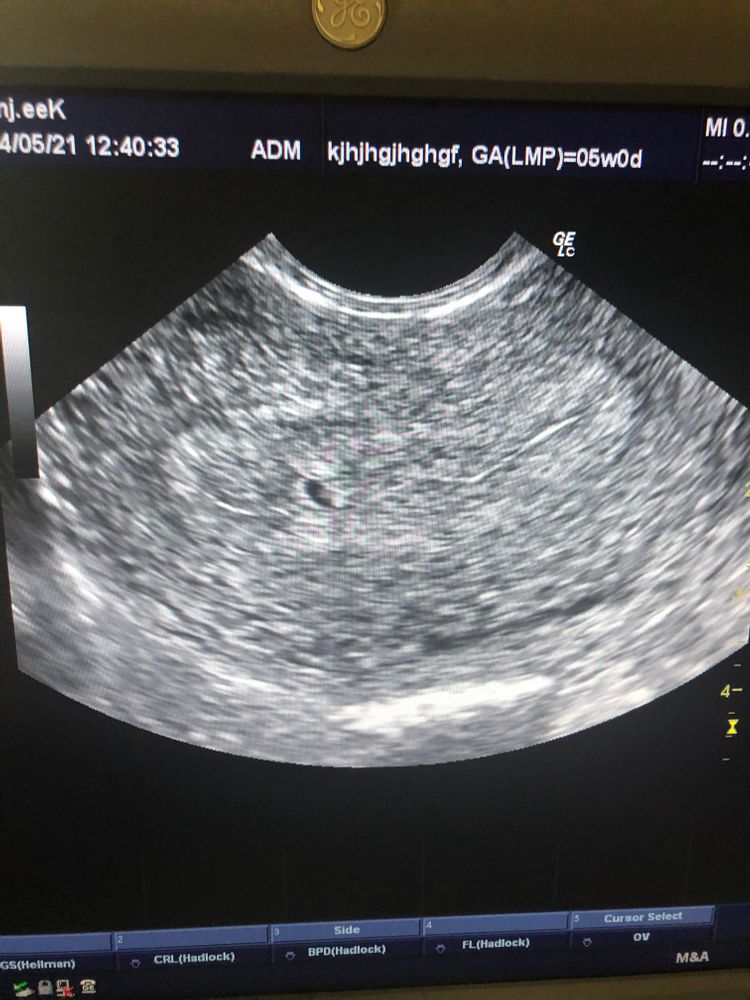

Анастасия в Копилка тестов // 5 лет Ну мы все))))🤰🏼Сегодня подтвердили маточную беременность и ПЯ 3,5 мм 🥰 У нас ПОЛУЧИЛОСЬ!!! (Финальный тест, пожелания) Посмотрите еще 20 записей на эту тему Отменить Ответить Kris Поздравляю 🙏 легкой беременности сердечко уже слышно ? 25.05.2021 Ответить Анастасия Kris, спасибо !!)) нет, сердечко ещё не слышно( 25.05.2021 Ответить Kati Супер! Поздравляю 🥳🥳🥳 24.05.2021 Ответить Евгения Шептунова Поздравляю 🎊лёгкой беременности 🎉 24.05.2021 Ответить Mouse Как здорово ! Поздравляем 🎊🍾 24.05.2021 Ответить Gerbera А сколько точно срок у Вас? 24.05.2021 Ответить Анастасия Gerbera , поставили 5 недель )) 24.05.2021 Ответить Gerbera 🙏🥳🥳🥳 24.05.2021 Ответить Динамика по Дпо Пост просто поделиться Чаты Беременных Выберите чат: Январята-2026 Февралята-2026 Мартята-2026 Апрелята-2026 Майчата-2026 Июнята-2026 Июлята-2026 Августята-2026